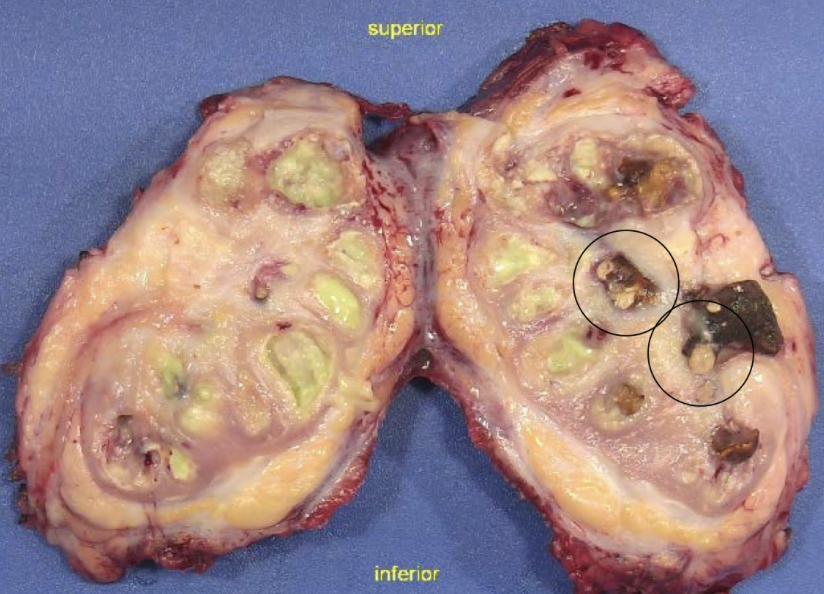

xanthogranulomatous pyelonephritis

proteus (>50%), E coli, pseudomonas, klebsiella

urine cultures negative!!

palpable mass that can mimic tumor

UT obstruction, staghorn, DM

xanthogranulomatous pyelonephritis

pus, scarring, stones

xanthogranulomatous pyelonephritis

sheets of foamy, lipid-laden macrophages